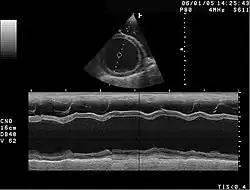

M mód (Movement mode) je způsob jednorozměrného zobrazení umožňující zobrazení pohybujících se struktur, nejčastěji srdce. Jde vlastně o A mód zobrazený v čase (na svislé ose je zobrazena hloubka a na vodorovné ose čas). Často se používá při vyšetření srdce jako součást echokardiografie.